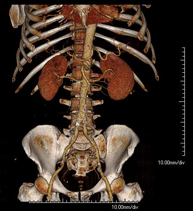

Prova diagnòstica no invasiva que consisteix en l'estudi de l'artèria aorta abdominal a través de l'obtenció d'imatges d'alta definició anatòmica mitjançant l'ús d'un equip de TC (Tomografia Computeritzada) i de contrast iodat. La qualitat de les imatges permet realitzar reconstruccions en 2D i 3D gràcies a estacions de treball especialitzades en l'estudi arterial. Està indicat en aquells pacients amb malaltia vascular (arteriosclerosi), en aneurismes d'aorta, en pacients amb dolor abdominal de possible origen vascular, en estudis prequirúrgics de lesions adjacents a l'aorta abdominal com a "mapa" vascular. La informació obtinguda de manera no invasiva és indispensable per als pacients que requereixen tractament percutani o quirúrgic. En aquells pacients que només requereixen seguiment de les lesions vasculars, aquesta tècnica és la tècnica no invasiva d'elecció juntament amb l'angio-RM. - Angio-TC Artèries renals

A non-invasive diagnostic test that involves studying the abdominal aorta by obtaining high-definition anatomical images using CT (computed tomography) equipment and iodinated contrast. With the aid of workstations specialised for arterial studies, the image quality supports 2D and 3D reconstructions. It is indicated in patients with vascular disease (atherosclerosis), aortic aneurysms, abdominal pain of possible vascular origin, pre-surgical studies of lesions adjacent to the abdominal aorta as a vascular ‘map’, etc. Information obtained non-invasively is indispensable for patients requiring percutaneous or surgical processing. In patients who only require tracking of vascular lesions, this technique is the non-invasive technique of choice, together with MRI angiography.